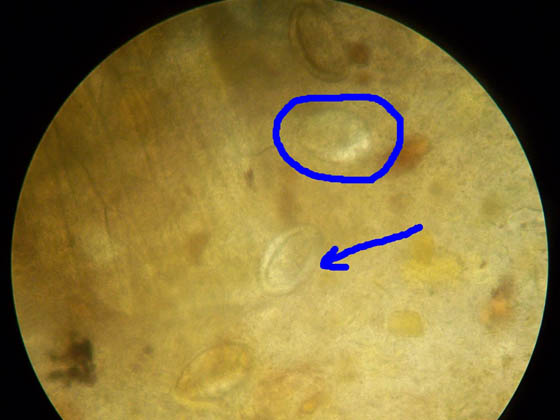

image

Яйца остриц под микроскопом